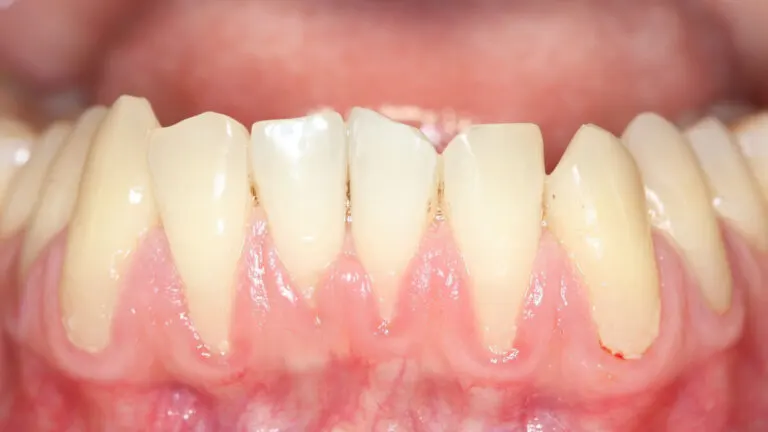

Algunas personas, cuando se miran al espejo, creen que tienen los dientes más largos de lo que sería normal. Además, es posible que noten que el tejido rosa sobre sus elementos dentarios aparenta ser más delgado. Pues bien, lo más probable es que padezcan un problema de encías retraídas.

La encía o tejido gingival es la parte blanda, firme y rosada que rodea el cuello de los dientes. Es decir, recubre lo que sería la raíz de los elementos dentarios, que en condiciones normales, no podemos ver.

Podemos decir que hay encías retraídas o recesión gingival cuando este tejido se desplaza, dejando visible la raíz. De acuerdo con una publicación científica del año 2015, la condición pone al descubierto la unión entre el cemento dental y el esmalte.

Por ello se provoca el efecto de «dientes más largos». En realidad, cada diente mide lo mismo, solo que ahora somos capaces de notar la raíz, que debería estar bajo la encía.

Más allá de afectar la estética y la apariencia de la sonrisa, hay consecuencias para la salud física al tener retracción gingival. En primera instancia, las raíces, que deberían estar protegidas, quedan susceptibles a la acción de la placa bacteriana.

Además, la raíz es muy sensible a los estímulos externos. Más de la mitad de los pacientes con este problema suelen tener sensibilidad dental, sobre todo al masticar o al cepillarse.